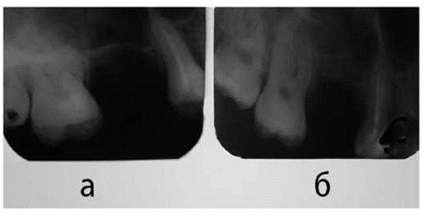

Рис. 2. Внутриротовая рентгенограмма альвеолярного отростка верхней челюсти справа:

а) до операции, б) через 3 месяца после операции

По данным анализа результатов оперативного закрытия ороантрального сообщения по нашим модификациям и последующего комплексного лечения, у всех больных получен положительный результат. В течение первой недели после операции отмечена умеренная припухлость в области соответствующей стороны подглазничой области. В тех случаях, когда произведена также радикальная гайморотомия, наблюдалось также сукровичное отделяемое из носа. Операционные раны зажили первичным натяжением у 25 больных. У 2-х больных в раннем послеоперационном периоде произошло частичное расхождение швов, что мы связываем с недостаточной мобилизацией слизисто-надкостничного лоскута в пределах альвеолярного отростка верхней челюсти и тканей преддверия полости рта. В этих случаях не приходилось производить повторную операцию. Раны зажили вторичным натяжением. Швы удалялись на 7-9-ые сутки. Эффективность предлагаемых методик оценивали по клинико-рентгенологическим данным. Внутриротовую рентгенографию производили через 7 дней после операции, к концу первого месяца и через 3 и 6 месяцев. Первые рентгенологические признаки образования молодой кости в области перфорационного отверстия (лунка удаленного зуба) появляются к концу 1-ого месяца. Далее процесс регенерации продолжается, к концу 3-его месяца на месте имплантируемого матрикса в комбинации с БоТП

Больной Г. 20 лет, обратился в клинику с жалобами на наличие сообщения полости рта и носа после удаления 16-ого зуба 3 месяца назад. При объективном осмотре больного со стороны внутренних органов отклонений от нормы не выявлено. При осмотре полости рта выявлен свищевой ход в области лунки 16-ого зуба, через который ротовая полость сообщалась с гайморовой пазухой (рис 3.1). Выделение гноя из носа со стороны гайморовой пазухи не определялось. На рентгенограмме в носолобной проекции вы-являлось правостороннее затемнение ВЧП (рис 1А). На внутриротовой рентгенограмме альвеолярного отростка верхней челюсти справа лунка 16-ого зуба сообщается с ВЧП (рис 2а). На основании клиникорентгенологических исследований диагностирован правосторонний перфоративный гайморит. Под общим обезболиванием произведена радикальная опера-ция ВЧП, с пластическим закрытием ороантрального сообщения. Предварительно освежали края лунки 16-ого зуба, затем проводили радикальную гайморотомию.

Контрольный осмотр больного Г. произведен через 3 месяца. Больной жалоб не предъявляет. Открывание рта свободное, слизистая оболочка преддверия полости рта по проекции удаленного зуба без особенностей, прослеживается тонкий послеоперационный рубец (рис 4). Пальпация безболезненна. На внутриротовой рентгенограмме в области лунки 16-ого зуба прослеживается новообразованная органотипичная костная ткань (рис 2.б). На рентгенограмме, произведенной в носолобной проекции, прозрачность правой ВЧП почти идентична с левой (рис 1Б). Интерес данного случая заключается в успешном пластическом закрытии ороантрального сообщения по предлагаемому нами способу.